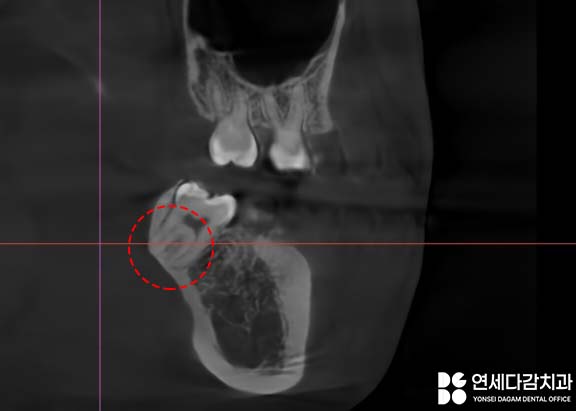

CT로 확인했을 때 사랑니의 뿌리가

아래턱뼈의 겉면인 치밀골 쪽으로

살짝 박혀있는 모습을 보일 수 있습니다.

그러나 진료하다 보면

거여동 치과 에서 보여드린 것처럼,

치근 일부가 단단한 치밀골에

박혀 있는 경우를 만나게 됩니다.

이런 상황에서는 발치 과정에서

치근이 부러지는 일이

생길 수 있습니다.

이는 구조적으로 충분히

일어날 수 있는 일이고,

흔한 일이기도 합니다.

구조적 특성에 따른

자연스러운 상황인 것이죠.